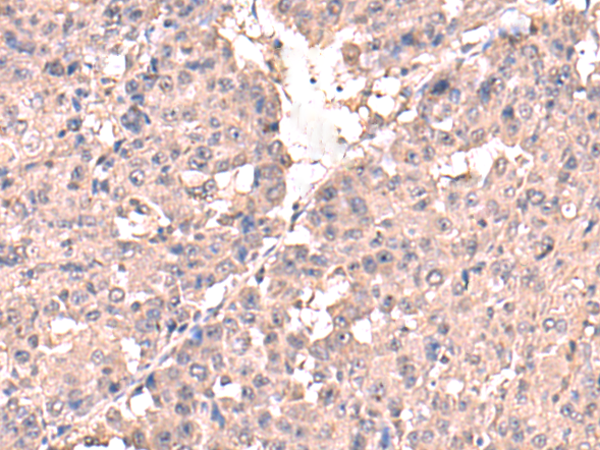

分类: 科研抗体货号: P08418别名: I; HSD3B; HSDB3; HSDB3A; SDR11E1; 3BETAHSD应用: WB,IHC反应种属: Human